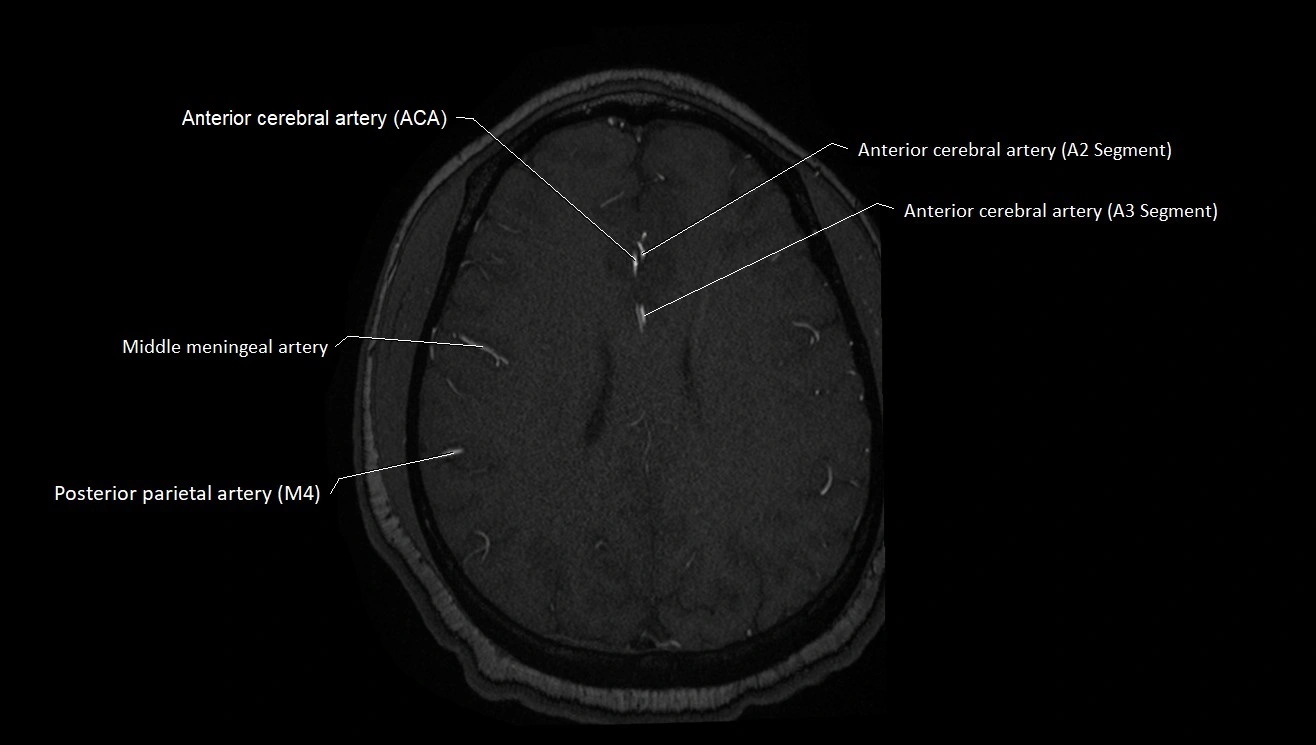

T1-weighted images:

• Vessel appears as a flow void (dark lumen) near the optic tract and temporal horn

• Surrounding parenchyma intermediate signal

T2-weighted images:

• Vessel lumen shows dark flow void

• Ischemic infarcts in its territory (internal capsule, thalamus) appear hyperintense

FLAIR:

• Vessel not seen directly; infarcts in AChA territory appear as hyperintense cortical/subcortical changes

• Chronic infarcts show gliotic hyperintensity

T1 Post-Gadolinium:

• Normal AChA enhances brightly and uniformly

• Abnormal focal enhancement indicates aneurysm, vasculitis, or AVM involvement